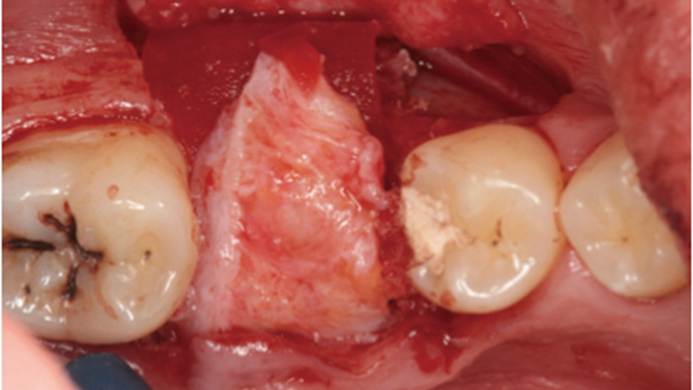

Clinical case: # 46 implant placement & GBR using i-Gen membrane for significant vertical resorption & mixed bone defect

AnyRidge, mandibular posterior, i-Gen, resorption, bone defect, bone regeneration, space management, #46, GBR, Dr. Iulian Filipov

AnyRidge implant system, i-Gen

“AnyRidge KnifeThread achieves excellent stability in regenerated bone & even in only 3mm bone height!”